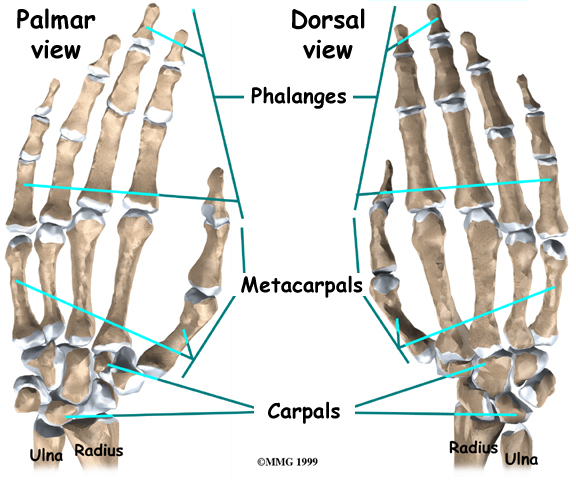

The anatomy of the wrist joint is extremely complex, probably the most complex of all the joints in the body. The joint is actually a collection of many joints and many bones. These joints and bones let us use our hands in many ways. The wrist must be extremely mobile to give our hands a full range of motion. At the same time, the wrist must provide the strength for heavy gripping.

The wrist is made up of eight separate small bones, called the:

Carpal Bones

The scaphoid bone is a carpal bone near the base of the thumb. The carpal bones connect the two bones of the forearm, the radius and the ulna, to the bones of the hand. The metacarpal bones are the long bones that lie underneath the palm.

The metacarpals attach to the phalanges, which are the bones in the fingers and thumb.

The metacarpals attach to the phalanges, which are the bones in the fingers and thumb.

One reason that the wrist is so complicated is because every small bone forms a joint with the bone next to it.

This means that what we call the wrist joint is actually made up of many small joints. Ligaments connect all the small bones to each other, and to the radius, ulna, and metacarpal bones.

The scaphoid bone is a small carpal bone on the thumb side (radial side) of the wrist. It is the most commonly fractured carpal bone.

This is probably because it actually crosses two rows of carpal bones, forming a hinge.